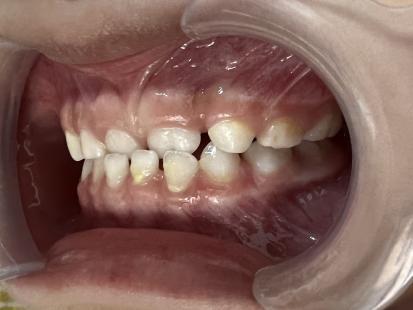

案例二:

治疗后